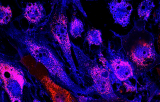

WT1 probe for FISH CE/IVD - Salivary gland cancers

The WT1 gene is located on 11p13 and encodes a zinc finger DNA-binding protein that acts as a transcriptional activator or repressor depending on the cellular or chromosomal context. Inactivating mutations in the tumor suppressor gene WT1 have been identified in patients with Wilms' tumor and in a subset of sporadic cancers. However, in desmoblastic small round cell tumors (DSRCT) recurrent translocations affecting the WT1 gene have been found. DSRCT is a highly aggressive mesenchymal tumor that primarily affects male adolescents and young adults. The translocation t(11;22)(p13;q12.2) is detectable in virtually all DSRCT tested and results in the fusion of the potent transcriptional activator domain of the EWSR1 gene and the DNA-binding zinc-finger domains of the WT1 gene. The EWSR1-WT1 chimeric protein acts as an oncogenic transcription factor as evidenced by its ability to transform cells in vitro. While EWSR1 rearrangements are present in about 90% of DSRCT but are also frequently found in other small round blue cell neoplasms as e.g. Ewing sarcoma, WT1 translocations are exclusively found in DSRCT. Hence, detection of the t(11;22) by Fluorescence in situ Hybridization represents a valuable tool for the differential diagnosis of DSRCT.